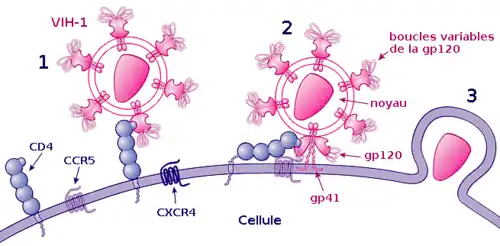

1) Fixation de la gp120 au récepteur CD4

2) Fixation d'une boucle variable de la gp120 au corécepteur et fixation de la gp41 sur la membrane cellulaire

3) Pénétration dans la cellule.

La fixation ou attachement à une cellule

Cette étape repose sur une reconnaissance entre les protéines de la surface virale gp120 et les récepteurs CD4 de la cellule cible. Après l'union avec un récepteur CD4, gp120 change de conformation et est attiré vers un corécepteur devant également être présent à côté de la molécule CD4. Plus d'une dizaine de corécepteurs ont été identifiés, mais les principaux sont CXCR4 pour les lymphocytes T CD4+ et CCR5 pour les macrophages[60].

La fusion, la pénétration et la décapsidation

C'est la seconde étape de l'infection, intervenant juste après l'union de gp120 avec le corécepteur. Cette union libère la protéine gp41, qui se fixe sur la membrane cytoplasmique. Par repli sur elle-même, gp41 attire l'enveloppe virale vers la membrane cytoplasmique, puis la fusion des membranes cellulaire et virale a lieu grâce à un peptide de fusion présent dans gp41. La capside du VIH pénètre alors dans le cytoplasme de la cellule ; une fois à l'intérieur de la cellule, elle se désagrège, libérant les deux brins d'ARN et les enzymes qu'elle contenait.

Ainsi, la protéine gp120 est responsable de l'attachement et gp41 de la fusion, puis de la pénétration au sein de la cellule.